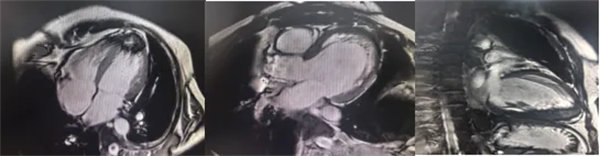

在常規心臟MRI檢查中,醫學影像科發現患者心肌異常表現,考慮鐵過載性心肌病,為明確診斷要進一步加做鐵定量技術,加掃T2 mapping序列。CMR鐵定量技術是目前評估心肌鐵含量的“金標準”,能夠快速、無創、精準量化心肌內鐵沉積程度,檢查結果提示患者局部心肌T2*值顯著低于正常范圍,符合鐵過載性心肌病的診斷標準。

基底部、中間部及心尖部 局部心肌T2*值明顯減低T2* 10-20/s, 部分小于10/s

心肌信號局部減低 呈現“黑色心肌”表現,這是由于鐵沉積導致局部磁場不均勻,引起信號丟失(失相位)。